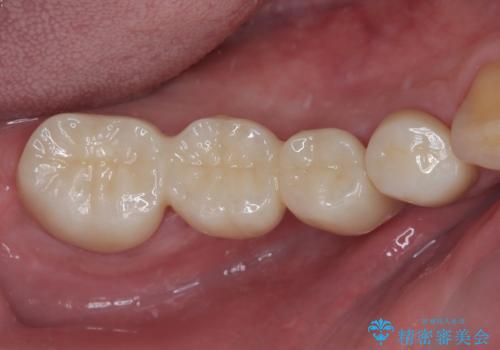

詰め物が割れた フルジルコニアクラウン

- 左下の4番目のセラミックの詰め物(セラミックインレー)が欠けたとのことで来院された患者様です。以前にセラミックの詰め物の治療を行い、噛み合わせが強く割れてしまっていました。今回はセラミックの詰め物のやり替えだとまた欠けてしまう可能性があるのでフルジルコニアクラウンでの治療を行うことにしました。拡大鏡視野下でセラミックの詰め物、虫歯を除去しフルジルコニアクラウンに適した形に整えました。

歯と歯茎の間に圧排糸と呼ばれる糸を入れてシリコーン印象を行いました。

見た目、機能面ともに満足していただけました。

噛み合わせが強い方なので今後はセラミックが割れないようにナイトガードを使っていただきながら、定期的にクリーニングで通ってもらう予定です。